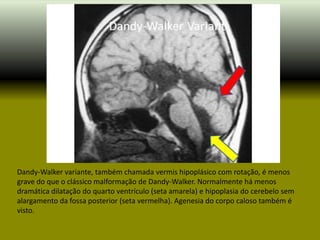

Dandy-Walker variante, também chamada vermis hipoplásico com rotação, é menos

grave do que o clássico malformação de Dandy-Walker. Normalmente há menos

dramática dilatação do quarto ventrículo (seta amarela) e hipoplasia do cerebelo sem

alargamento da fossa posterior (seta vermelha). Agenesia do corpo caloso também é

visto.